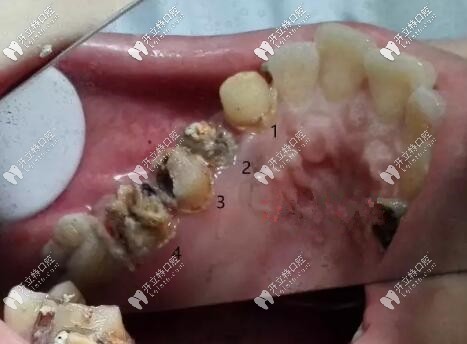

前方高能,看看拆掉口的基牙,我這種情況只能拔掉做種植牙了。

烤瓷冠拆掉后基牙圖片

烤瓷牙尤其那種連著做的連橋冠太多的,兩端基牙承受不住咬合,長時間就會有縫隙,很容易導(dǎo)致基牙齲壞。

烤瓷牙會刺激牙齦,導(dǎo)致牙齦萎縮,牙冠與基牙不貼合,建議大家要做也做全瓷牙,基牙齲壞幾率會小一些。